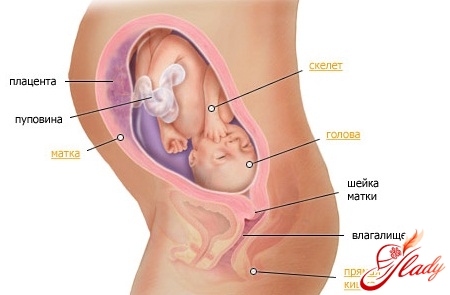

Беременность 29 неделя – это то время, когда малыш начинает готовиться к самостоятельной жизни, вне полости матки. Он уже научился регулировать температуру своего тела, а выработку красных клеток крови полностью взял на себя костный мозг ребенка. Ребенок активно мочится – в день он выделяет не менее полулитра мочи. Его движения стали совершенно иными, если раньше он кувыркался и выполнял различные акробатические трюки, то сейчас он все больше работает локтями и коленями – места в матке уже маловато, а вот сил и упорства заметно прибавилось.

Жировая прослойка увеличивается и скоро достигнет 4% от общей массы тела. В селезенке уже начали образовываться кровяные клетки, ответственные за иммунитет. Но именно ваши антитела способны защитить его после рождения, поэтому так важно как можно дольше кормить ребенка грудью. На зубах, которые спрятаны в деснах уже сформирована эмаль. И, если вся беременность прошла без осложнений, то зубы вашего малыша будут здоровыми и крепкими. Беременность 29 неделя УЗИ обследование показывает, что масса ребенка около 1350-ти граммов, при росте в 26 см. Преждевременные роды на данном этапе в 90% случаев заканчиваются без осложнений.

Беременность 29 неделя симптомы: чем ближе к родам, тем сильнее проявляется дискомфорт у мам. Из-за растущего плода внутренние органы меняют свое месторасположение, и многим из них приходится потесниться. Правильная осанка, адекватные физические нагрузки и хорошее питание – вот залог хорошего самочувствия будущей мамы. Поскольку на мочевой пузырь оказывается значительное давление увеличенной маткой, то женщине приходится чаще ходить в туалет, что иногда может вызвать неприятные ощущения.